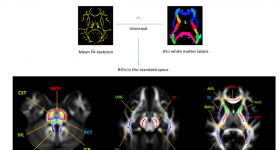

本文使用先進(jìn)的擴(kuò)散磁共振成像(dMRI)研究了中青年人腦白質(zhì)的微觀結(jié)構(gòu)變化。使用混合擴(kuò)散成像(HYDI)獲得多shell...